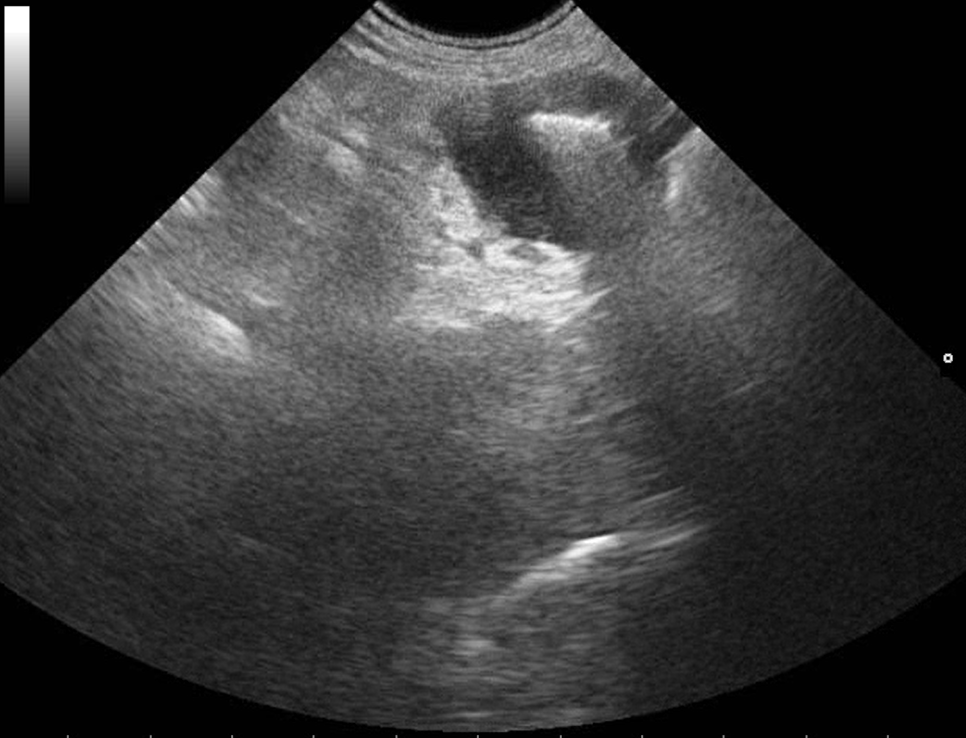

Webinář zaměřen na klinicky orientovanou sonografii gastrointestinálního traktu, se zaměřením na patologické nálezy, které mají přímý dopad na další diagnostický a terapeutický postup. Čeká na vás více než 50 komentovaných videosmyček z reálných klinických případů.